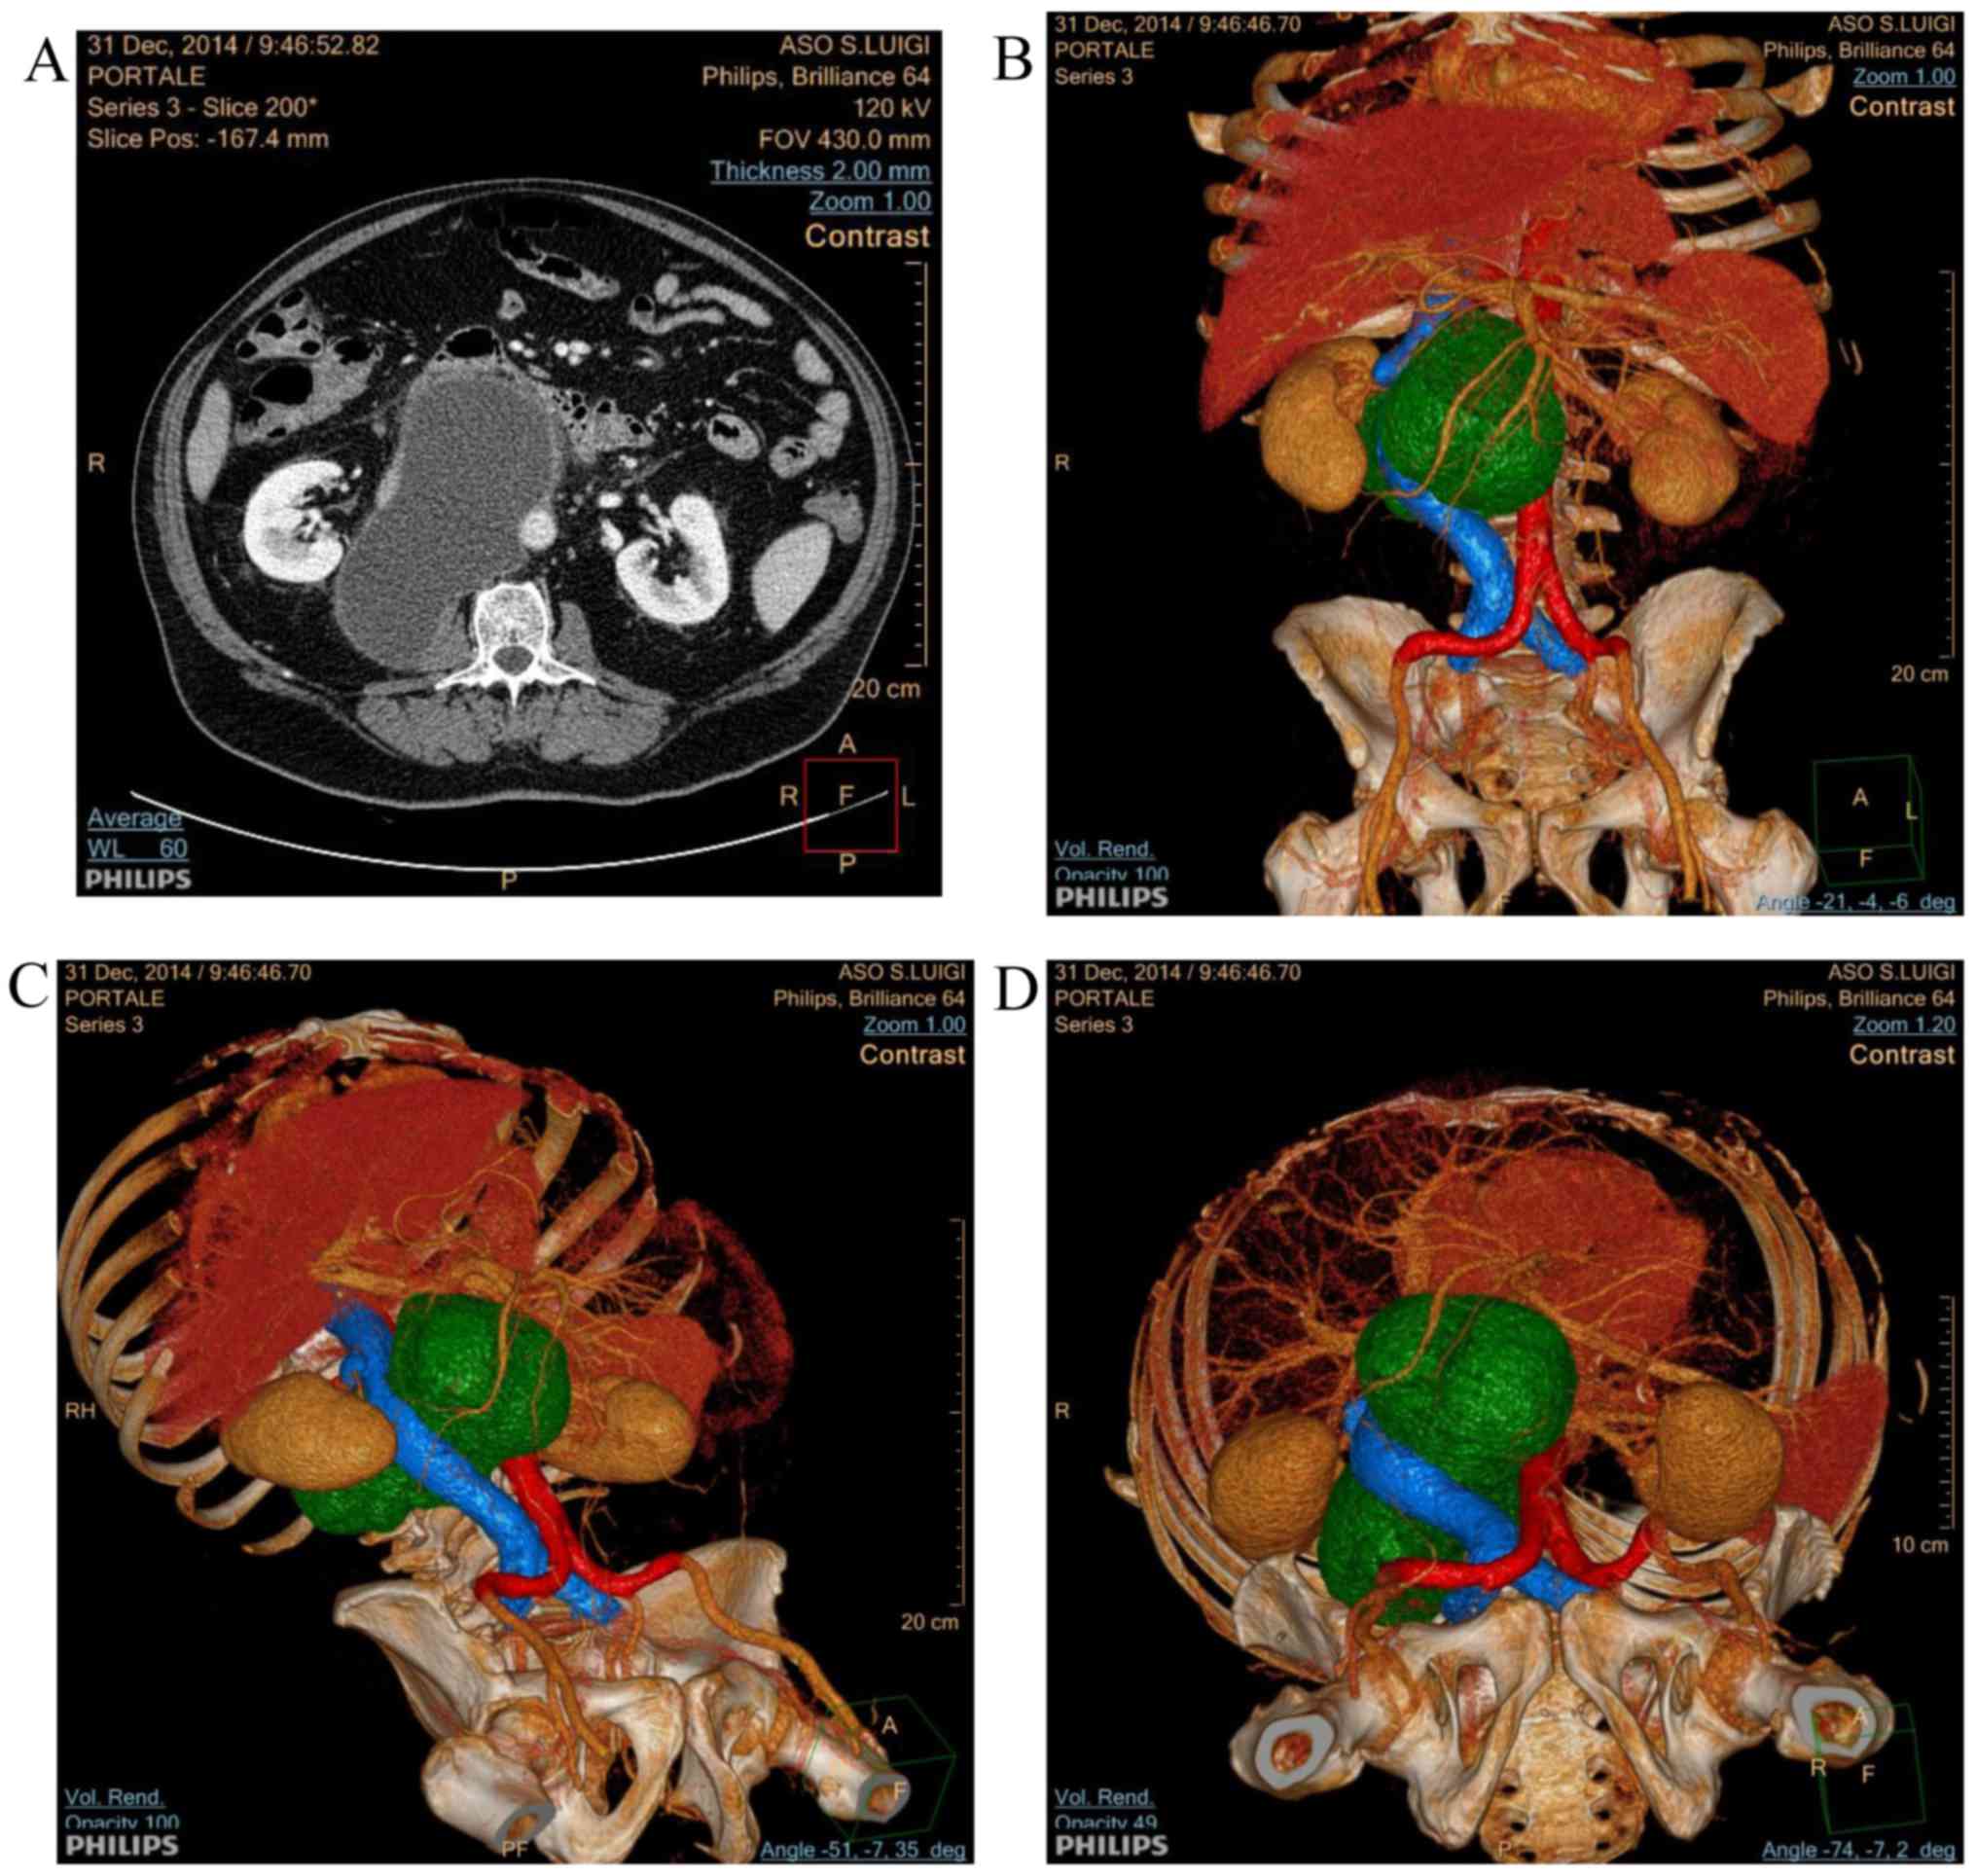

Detection and management of retroperitoneal cystic lesions: A case report and review of the literature

The identification of cystic lesions within the retroperitoneal space is a rare event that poses clinicians the challenge of a difficult diagnosis and disease management. Retroperitoneal cystic lesions account for a group of lesions that range from common benign lesions (e.g., lymphoceles developing as a surgical complication) to rare aggressive malignant neoplasms. Currently, in the majority of cases, image‑guided procedures allow for a pathological diagnosis to be achieved in these challenging lesions, thus offering the chance of an appropriate treatment; however, the overall clinical assessment of retroperitoneal cysts is highly demanding. The present study reports the management of a representative clinical case, presenting with a voluminous cystic mass able to dislocate cave vein, whose diagnosis was preceded by a deep vein thrombosis. Computed tomography‑scan and ultrasound guided percutaneous drainage were performed to achieve the diagnosis. Following the discussion of the current case report, a review of the pathological and radiological characteristics of retroperitoneal cystic lesions is presented.

Figure 1